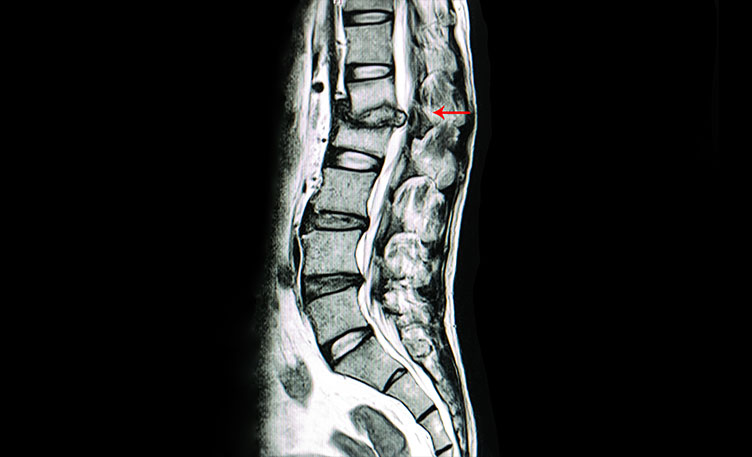

Spine Tuberculosis Treatment In Nashik

Spinal tuberculosis is one of the oldest diseases known to mankind and has been found in Egyptian mummies dating back to 3400 BC.

The disease is popularly known as Pott's spine. The name traces back its origin from the description of tuberculous infection of the spine by Sir Percival Pott in his monograph in 1779.